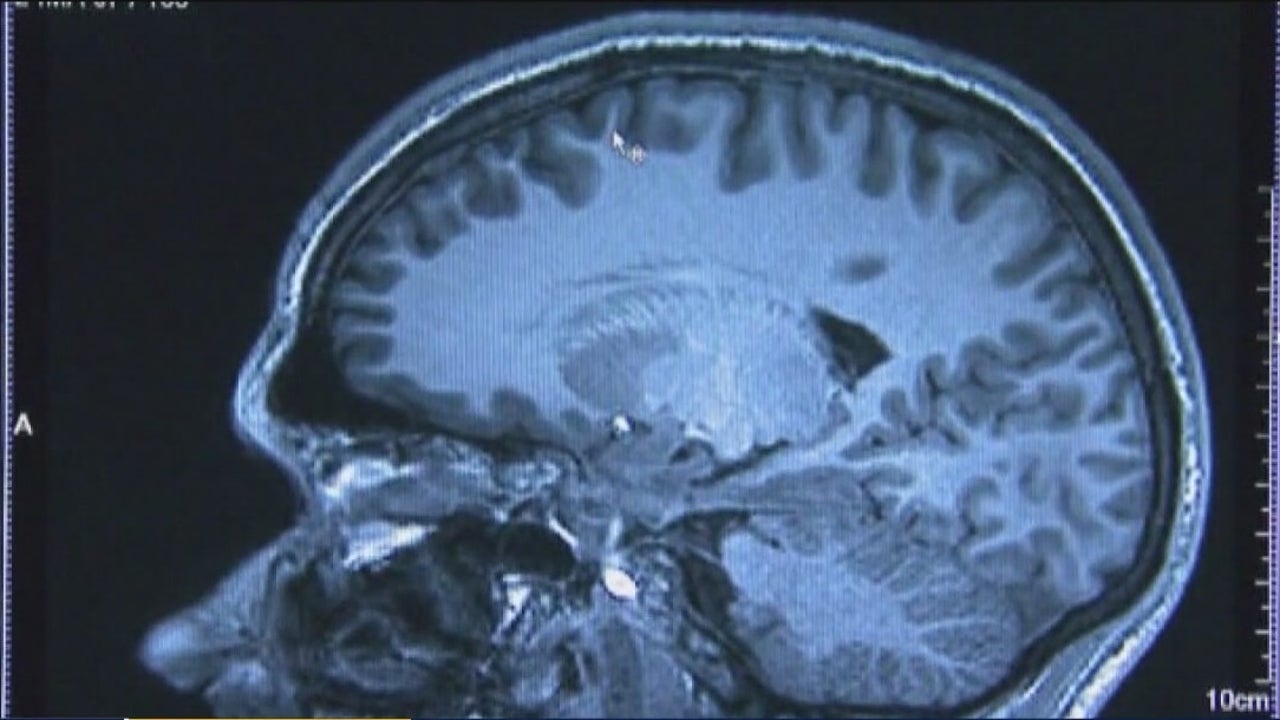

In the first of it’s kind procedure, surgeons implanted a small device under the scalp of the patients which wired directly to the section of the brain known for regulating satisfaction and reward. The device sends an electrical jolt to the region which scientists say effectively lowers the craving for food.